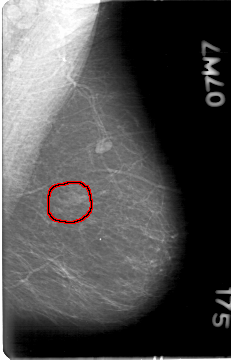

D_4028_1.LEFT_MLO

LEFT_MLO LINES 5386 PIXELS_PER_LINE 3451 BITS_PER_PIXEL 12 RESOLUTION 43.5 OVERLAY

FILE: D_4028_1.LEFT_MLO.OVERLAY

TOTAL_ABNORMALITIES 1

ABNORMALITY 1

LESION_TYPE MASS SHAPE LOBULATED MARGINS OBSCURED

ASSESSMENT 0

SUBTLETY 4

PATHOLOGY BENIGN

TOTAL_OUTLINES 1

BOUNDARY